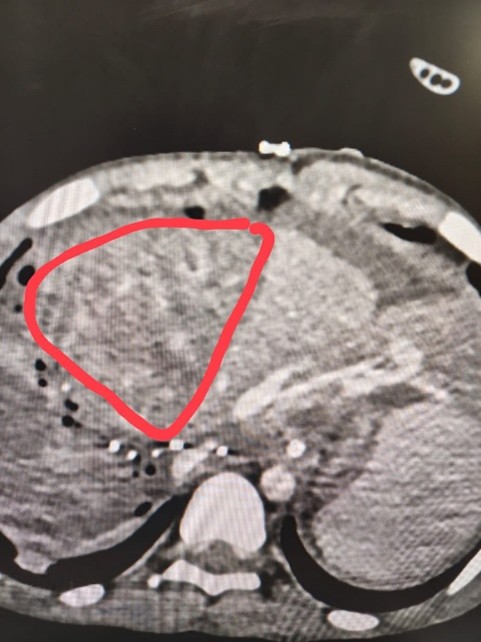

An ultra-short case report: Middle Hepatic Vein (MHV) stenosis

A 11-year-old patient underwent liver transplant, 24 hrs later, the liver enzymes were very high and surveillance USG showed no flow in MHV.

Immediately CECT was done which showed congestion in right lobe.

There was a tight stenosis at the anastomotic site of MHV and IVC.